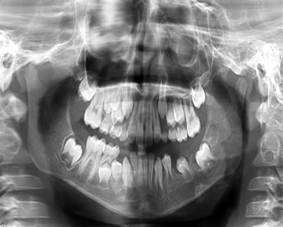

Este paciente ha estado en seguimiento en consulta externa de Cirugía Maxilofacial durante un año, realizándose los chequeos radiográficos periódicos pertinentes, a los 3, 6 y 12 meses respectivamente como se puede ver en las (Figuras 5, Figura 6 y Figura7).

Pasado este año se puede ver la recuperación total de la zona intervenida y desde el punto vista clínico el niño está bien, desempeñándose en sus actividades diarias sin ninguna dificultad.